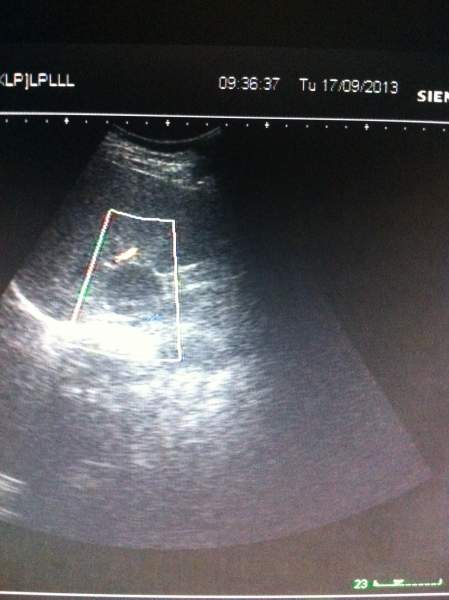

超声图像,各位大侠帮忙看下,肝上的这块是不是占位? 已有2人参与

患者今天前到我单位体检,两月前在另一单位体检过,结果正常,这次看肝上像有异常回声,让她再去上级单位复查,第二天患者去了,复查结果说是正常。 难道我们图像显示的是肝尾叶?回声可以这么低吗?看着还有边界的样子,难道是部分容积效应?真心很纠结,求指教,谢谢! IMG_1411.JPG IMG_1412.JPG IMG_1413.JPG IMG_1416.JPG |